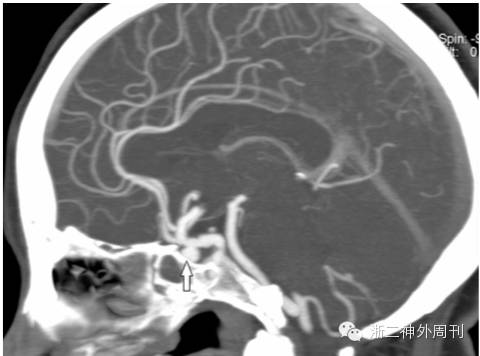

一个月后患者因接连两次突发口鼻大出血(总出血量约达800~1000ml)再次急诊入院。查体示急性休克病容,予抗休克处理后行急诊头颅CT及CTA检查,提示右侧颈内动脉假性动脉瘤伴眼眶内异物残留(图6)。

图6. CT及CTA提示眶后异物残留,右颈内动脉假性动脉瘤。

与家属沟通后,采取后者方案。BOT及加强试验阴性后,行弹簧圈加球囊将右侧颈内动脉及假性动脉瘤一起闭塞(图7)。

图7. 右颈内动脉及假性动脉瘤闭塞,前交通侧枝循环良好。